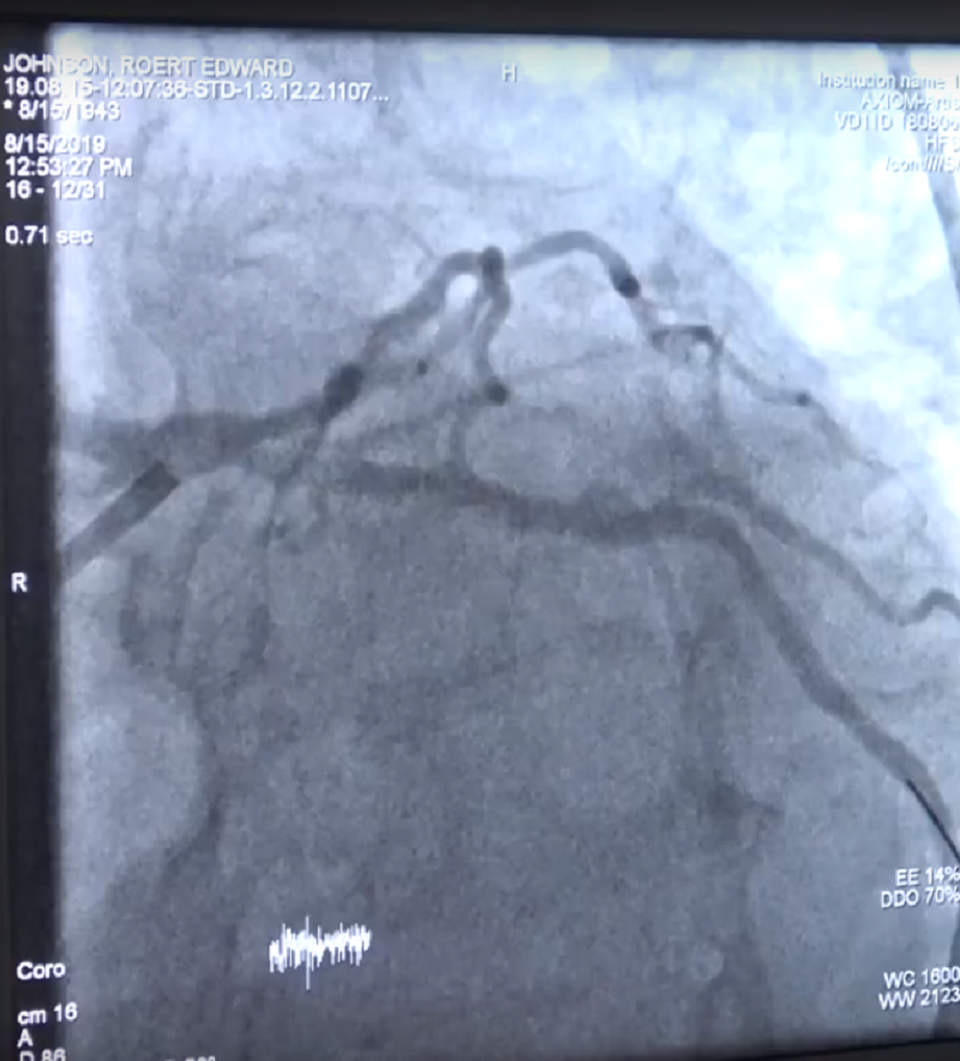

Hình ảnh chụp mạch máu xóa nền ghi nhận tình trạng của người bệnh

Các bác sĩ đã thống nhất hội chẩn với chẩn đoán, nhồi máu cơ tim cấp giờ thứ 3. Hình ảnh chụp mạch máu của bệnh nhân cho thấy động mạch mũ đoạn giữa gần như bị tắc hoàn toàn (tắc 90%). BS Tạ Anh Hoàng, khoa Tim mạch, Bệnh viện Quân Y 175 cho hay: “Đây là ca bệnh nặng, nguy cơ tử vong cao, bệnh nhân có chỉ định can thiệp động mạch vành cấp cứu. Sau 45 phút khẩn trương, chúng tôi đã tiến hành nong bóng, đặt stent khôi phục dòng chảy cho bệnh nhân”.